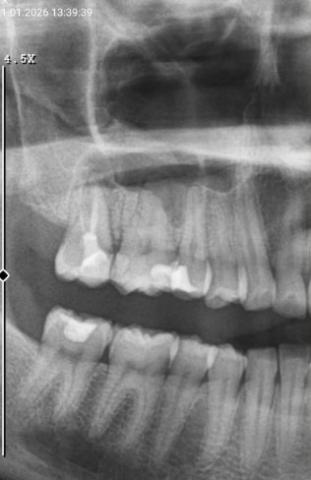

The dental X-ray shows bone changes around the roots of the teeth, particularly in the back tooth area. There are visible signs of bone loss and darkened areas near the root tips, which commonly indicate a tooth abscess or chronic dental infection.

Some teeth appear previously treated, but the surrounding bone suggests ongoing or unresolved infection.

Full Analysis and Provisional Diagnosis

Based on the X-ray appearance, the most likely findings include:

Periapical infection at the tooth root

Bone loss caused by long-standing infection

Possible failure or reinfection of a treated tooth

Reduced bone support around affected teeth

A clinical examination and comparison with earlier X-rays are required to confirm activity of the infection.

This X-ray shows bone infection around tooth roots, often without obvious pain at first. Early dental intervention is critical to preserve bone, prevent abscess spread, and protect overall oral health.